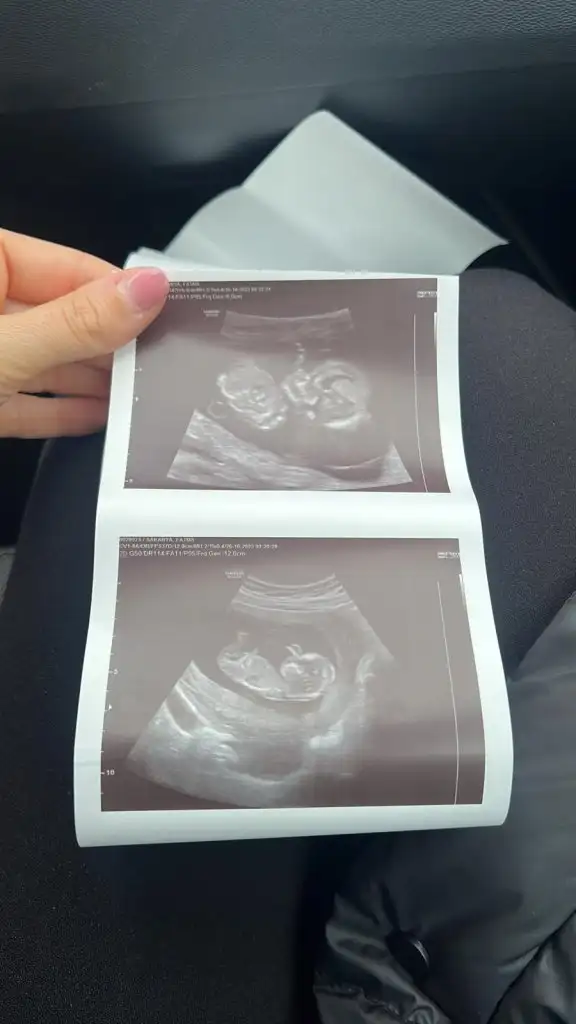

Merhaba kızlar bizde 11 hafta 2 günlük nasıl anlıyorsunuz bizede yorum. Yaparmısınız

12 haftalik

Eklentiler

• IMG-20231026-WA0002.webp

31,3 KB · Görüntüleme: 48

• IMG-20231026-WA0001.webp

18,8 KB · Görüntüleme: 46

• IMG-20231026-WA0000.webp

15,9 KB · Görüntüleme: 40